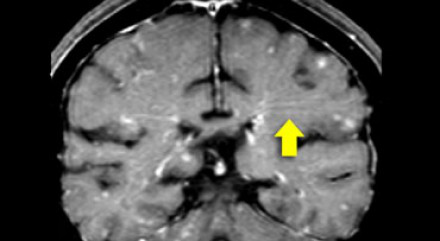

多發(fā)斑塊狀病灶的鑒別診斷

圖片一

在上圖中,是各種多發(fā)性點狀和斑塊狀白質(zhì)病灶圖像,我們對其中部分病例進行詳細討論。需要說明的是,以下鑒別診斷中提到的疾病與上圖中的圖像并不完全重合。

交界區(qū)腦梗死

MRI成像病灶要點:一般來說,這些病灶僅位于一個腦半球,要么位于深層白質(zhì)與灰質(zhì)的分水嶺區(qū)域(watershed area),要么位于周圍的分水嶺區(qū)域。在上圖中,病灶位于深層的分水嶺區(qū)域。

急性播散性腦脊髓炎(ADEM)

MRI成像病灶要點:在感染或接種疫苗后10-14天,多個局灶性病灶出現(xiàn)在腦白質(zhì)和基底節(jié)。與MS一樣,ADEM病變可累及脊髓、U形纖維以及胼胝體,有時可出現(xiàn)增強病灶。與MS所不同的是,ADEM的病灶通常更大,且好發(fā)于青年人,病程是單相的。

萊姆病

病灶大小約為2-3毫米,與MS的病灶相似,但患者會有皮疹和其他流感樣疾病。脊髓呈現(xiàn)高信號,CN7(神經(jīng)根入腦干區(qū))信號增強。

肉樣瘤

肉樣瘤的病灶分布與MS非常相似。

進行性多灶性白質(zhì)腦病(PML)

PML是一種由JC病毒感染引起的脫髓鞘性疾病,常見于免疫抑制患者。

MRI成像病灶要點:白質(zhì)損傷病灶在U形纖維的間隙占位,不增強,與HIV或CMV不同。

PML的病灶可在單側(cè)出現(xiàn),但更常見的是呈雙層、不對稱性分布。

血管周圍間隙(Virchow Robin spaces)

MRI成像病灶要點:T2加權(quán)成像明亮,F(xiàn)LAIR成像黑暗。

小血管性疾病

白質(zhì)損傷病灶位于深層白質(zhì)區(qū)域,不位于胼胝體、腦室旁或皮層旁。